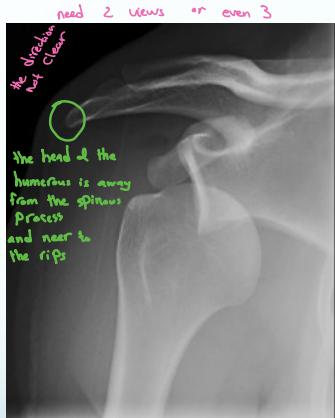

X-ray Findings:

- AP view:

- The humeral head is medially rotated → “Electric light bulb” sign

- The empty glenoid sign

- Posterior displacement

- Axillary & Scapular views are essential

- Rule-out fractures: neck, lesser tuberosity, glenoid

- CT Scan if still in doubt